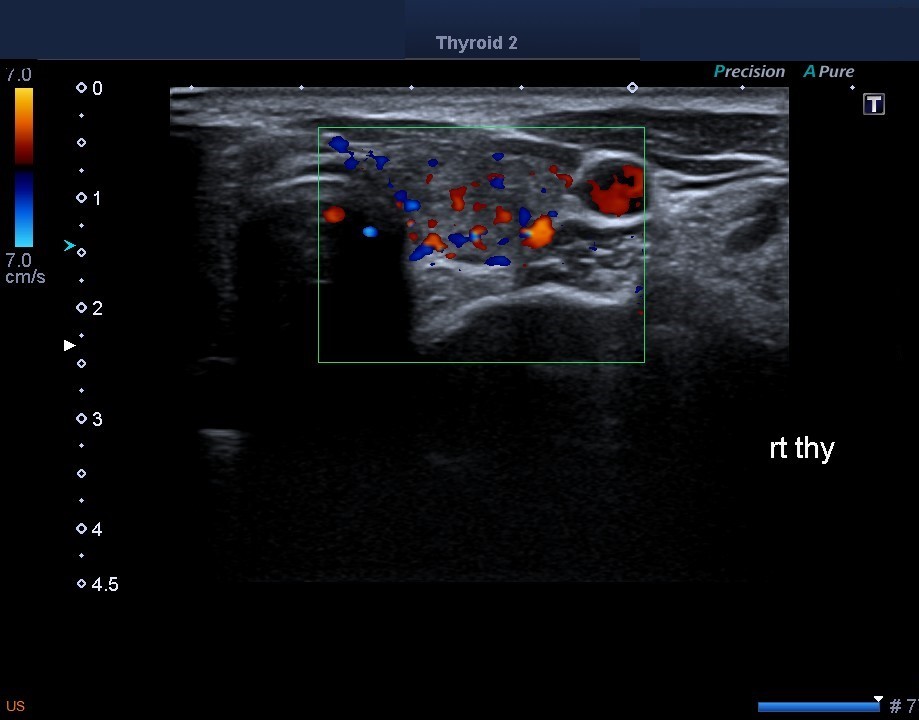

圖一(甲狀腺炎 超音波照  /  佳齡生活健康中心 耳鼻喉科主治醫師 孫強醫師提供 )

圖二(甲狀腺結節 超音波照  /  佳齡生活健康中心 耳鼻喉科主治醫師 孫強醫師提供 )

圖三(甲狀腺癌 超音波照  /  佳齡生活健康中心 耳鼻喉科主治醫師 孫強醫師提供 )